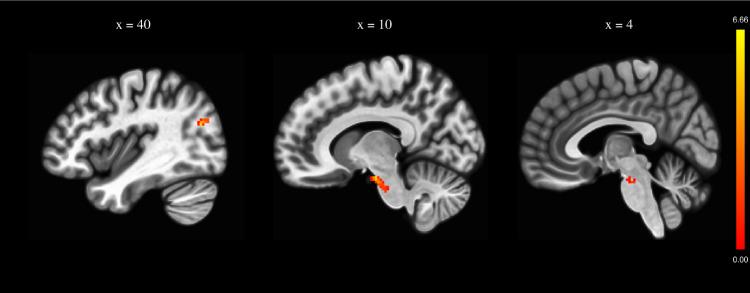

Optimal noninvasive brain stimulation parameters for the treatment of negative symptoms of schizophrenia remain unclear. Here, we aimed to investigate the clinical and biological effects of intermittent theta burst transcranial magnetic stimulation (iTBS) in patients with treatment-resistant negative symptoms of schizophrenia (NCT00875498). In a randomized sham-controlled 2-arm study, 22 patients with schizophrenia and treatment-resistant negative symptoms received 20 sessions of either active (n = 12) or sham (n = 10) iTBS. Sessions were delivered twice a day on 10 consecutive working days. Negative symptom severity was assessed 5 times using the Scale for the Assessment of Negative Symptoms (SANS): before iTBS, after iTBS, and 1, 3, and 6 months after iTBS. As a secondary objective, we explored the acute effects of iTBS on functional connectivity of the left dorsolateral prefrontal cortex (DLPFC) using seed-based resting-state functional connectivity MRI (rsFC fMRI) images acquired before and after iTBS. Active iTBS over the left DLPFC significantly decreased negative symptoms severity compared to sham iTBS (F = 3.321, p = 0.026). Post hoc analyses revealed that the difference between groups was significant 6 months after the end of stimulation sessions. Neuroimaging revealed an increase in rsFC between the left DLPFC and a brain region encompassing the right lateral occipital cortex and right angular gyrus and a right midbrain region that may encompass dopamine neuron cell bodies. Thus, iTBS over the left DLPFC can alleviate negative symptoms of schizophrenia. The effect might be driven by significant modulation of dopamine transmission.

用于治疗精神分裂症阴性症状的最佳非侵入性脑刺激参数仍不明确。在此,我们旨在研究间歇性theta爆发式经颅磁刺激(iTBS)对难治性精神分裂症阴性症状患者的临床和生物学效应(NCT00875498)。在一项随机假对照双臂研究中,22例患有难治性精神分裂症阴性症状的患者接受了20次主动iTBS(n = 12)或假iTBS(n = 10)治疗。在连续10个工作日内,每天进行两次治疗。使用阴性症状评估量表(SANS)在iTBS治疗前、治疗后以及治疗后1、3和6个月对阴性症状严重程度进行了5次评估。作为次要目标,我们使用iTBS治疗前后采集的基于种子点的静息态功能连接MRI(rsFC fMRI)图像,探索了iTBS对左侧背外侧前额叶皮质(DLPFC)功能连接的急性效应。与假iTBS相比,左侧DLPFC的主动iTBS显著降低了阴性症状严重程度(F = 3.321,p = 0.026)。事后分析显示,刺激疗程结束后6个月,两组之间的差异具有显著性。神经影像学显示,左侧DLPFC与一个包含右侧枕叶外侧皮质和右侧角回以及一个可能包含多巴胺神经元细胞体的右侧中脑区域之间的rsFC增加。因此,左侧DLPFC的iTBS可以缓解精神分裂症的阴性症状。这种效应可能是由多巴胺传递的显著调节驱动的。